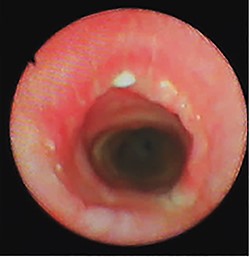

A non-smoker 31-year-old female with a history of Turner syndrome and Follicular thyroid carcinoma treated by total thyroidectomy and radical neck dissection, presented to her follow-up visit at the oncology department. The patient did not report symptoms such as dyspnea, cough, wheezing, or neck masses. No tumors or abnormal breath sounds were present during the physical examination. The follow-up computed tomography (CT) scan incidentally showed a partial airway obstruction secondary to a 14 mm endotracheal tumor (Fig. 1). There were no lymphadenopathy or mediastinal masses. Flexible bronchoscopy confirmed a 14 × 8 × 5 mm, smooth and oval-shaped tumor at the left posterior tracheal wall.

(A) CT scan showing an endotracheal tumor at the left posterior tracheal wall; (B) bronchoscopy view showing partial airway obstruction caused by the tumor.